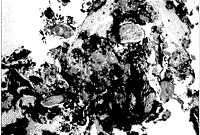

毛干、皮脂腺和炎性细胞